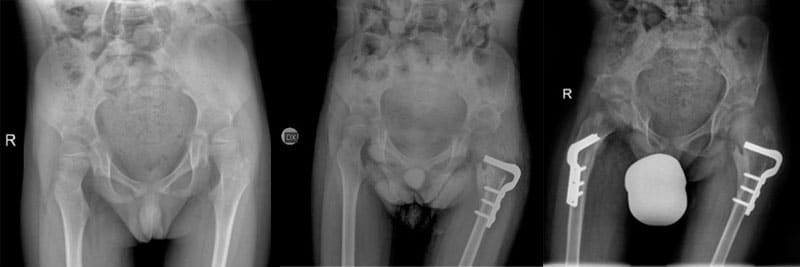

Lo scopo del lavoro è stato quello di valutare i risultati della ricostruzione dell’anca come trattamento chirurgico per la lussazione dell’anca nei bambini affetti da paralisi cerebrale infantile.

La tecnica utilizzata è quella di ridirezionare le ossa del femore e del bacino dopo averle sezionate, per far si che l’articolazione dell’anca sia di nuovo di forma e funzione normale.

I pazienti sono stati sottoposti a studio radiografico preoperatorio e poi a 6 e 12 mesi, e successivamente ogni anno.